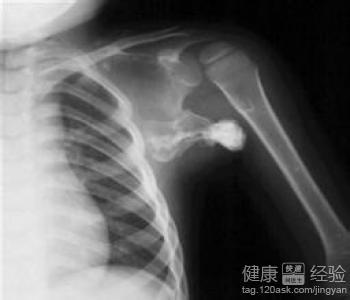

骨癌片子

骨癌ct图片

骨癌的早期小肿块图片

骨癌是什么样子的图片

骨癌图片高清图片

骨癌的早期症状图

骨癌骨头图片

骨癌图片